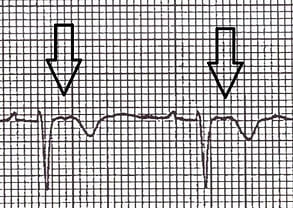

2. Epsilon wave in V2 (a distinctive wave at the end of the complex and beginning of the ST segment)

Epsilon wave (30% of patients, most specific finding)

T wave inversion in V1-V3 (seen in 85% of patients)

Prolonged S-wave upstroke in V1-V3 (95% of patients)

QRS widening in V1-V3

Fontaine leads

Fontaine bipolar precordial leads (F-ECG) are used to increase the sensitivity of epsilon wave detection. Leads are placed as shown:

Right Arm (RA) over the manubrium.

Left Arm (LA) over the xiphoid process.

and Left Leg (LL) in the standard V4 position (5th ICS MCL).